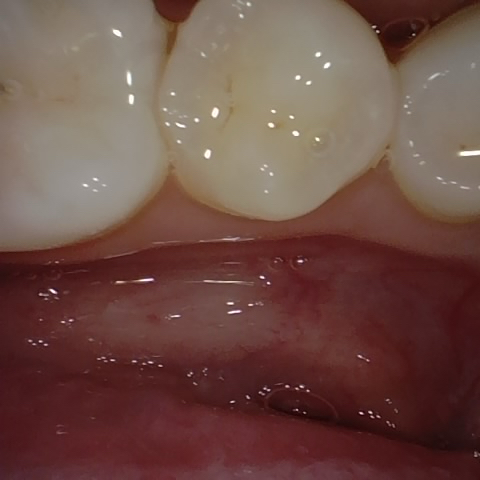

Annotated as "Bad"